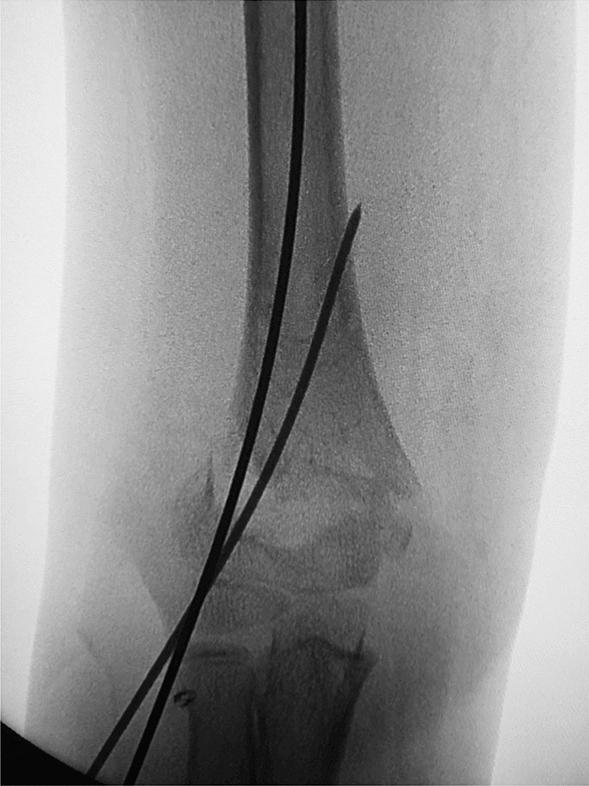

一种新的髓内弹性复位技术,用于治疗儿童 Gartland Ⅲ型肱骨髁后外侧移位髁上骨折的“变钝”克氏针。

A new technique of intramedullary elastic reduction of the "de-sharpened" Kirschner wire for the treatment of Gartland type III posterolateral displaced supracondylar fracture of the humerus in children.

To compare the clinical effects of intramedullary elastic reduction of the "de-sharpened Kirschner wire and traditional three-dimensional manipulation in the treatment of Gartland type III posterolateral supracondylar fracture of the humerus in children.

METHODS

A retrospective cohort analysis was made on 106 cases of Gartland type III posterolateral supracondylar fracture of the humerus treated in the Department of Orthopaedics of a Children's Hospital from March 2020 to March 2022. According to different surgical technology, the patients were divided into two groups: intramedullary elastic reduction of the de-sharpened Kirschner wire group (experimental group, n = 50) and traditional three-dimensional manipulation group (control group, n = 56). The surgical operating time, intraoperative fluoroscopy times, postoperative Baumann angle changes, postoperative elbow function Flynn score, and complications were collected and compared between the two groups.

RESULTS

All the enrolled cases underwent surgery successfully and were followed-up at least 6 months. The surgical operating time of the experimental group was 32.88 ± 3.69 min and that of the control group was 45.56 ± 10.13 min, and the difference was statistically significant (P < 0.05). The intraoperative fluoroscopy times were 20.62 ± 5.41 times in the experimental group and 32.48 ± 8.20 times in the control group (P < 0.05). The change of Baumann angle in the experimental group after operation was 2.3 ± 1.3 and that in the control group was 6.0 ± 2.1 (P < 0.5). Elbow joint Flynn scoring standard to evaluate the curative effect: the excellent and good rate was 98.00% (49/50) in the experimental group and 92.86% (52/56) in the control group (P > 0.5). There were no complications such as osteomyelitis, compartment syndrome, iatrogenic vascular and nerve injury, and myositis ossificans in either group.

CONCLUSIONS

Good functional outcome can be obtained with both intramedullary elastic reduction of the de-sharpened Kirschner wire and traditional three-dimensional manipulation for Gartland type III posterolateral displaced supracondylar fracture of the humerus in children; however, the former does not need repeated manipulation, and the operation time is shorter, the number of intraoperative fluoroscopy is less, and the recovery of the Baumann angle is better.